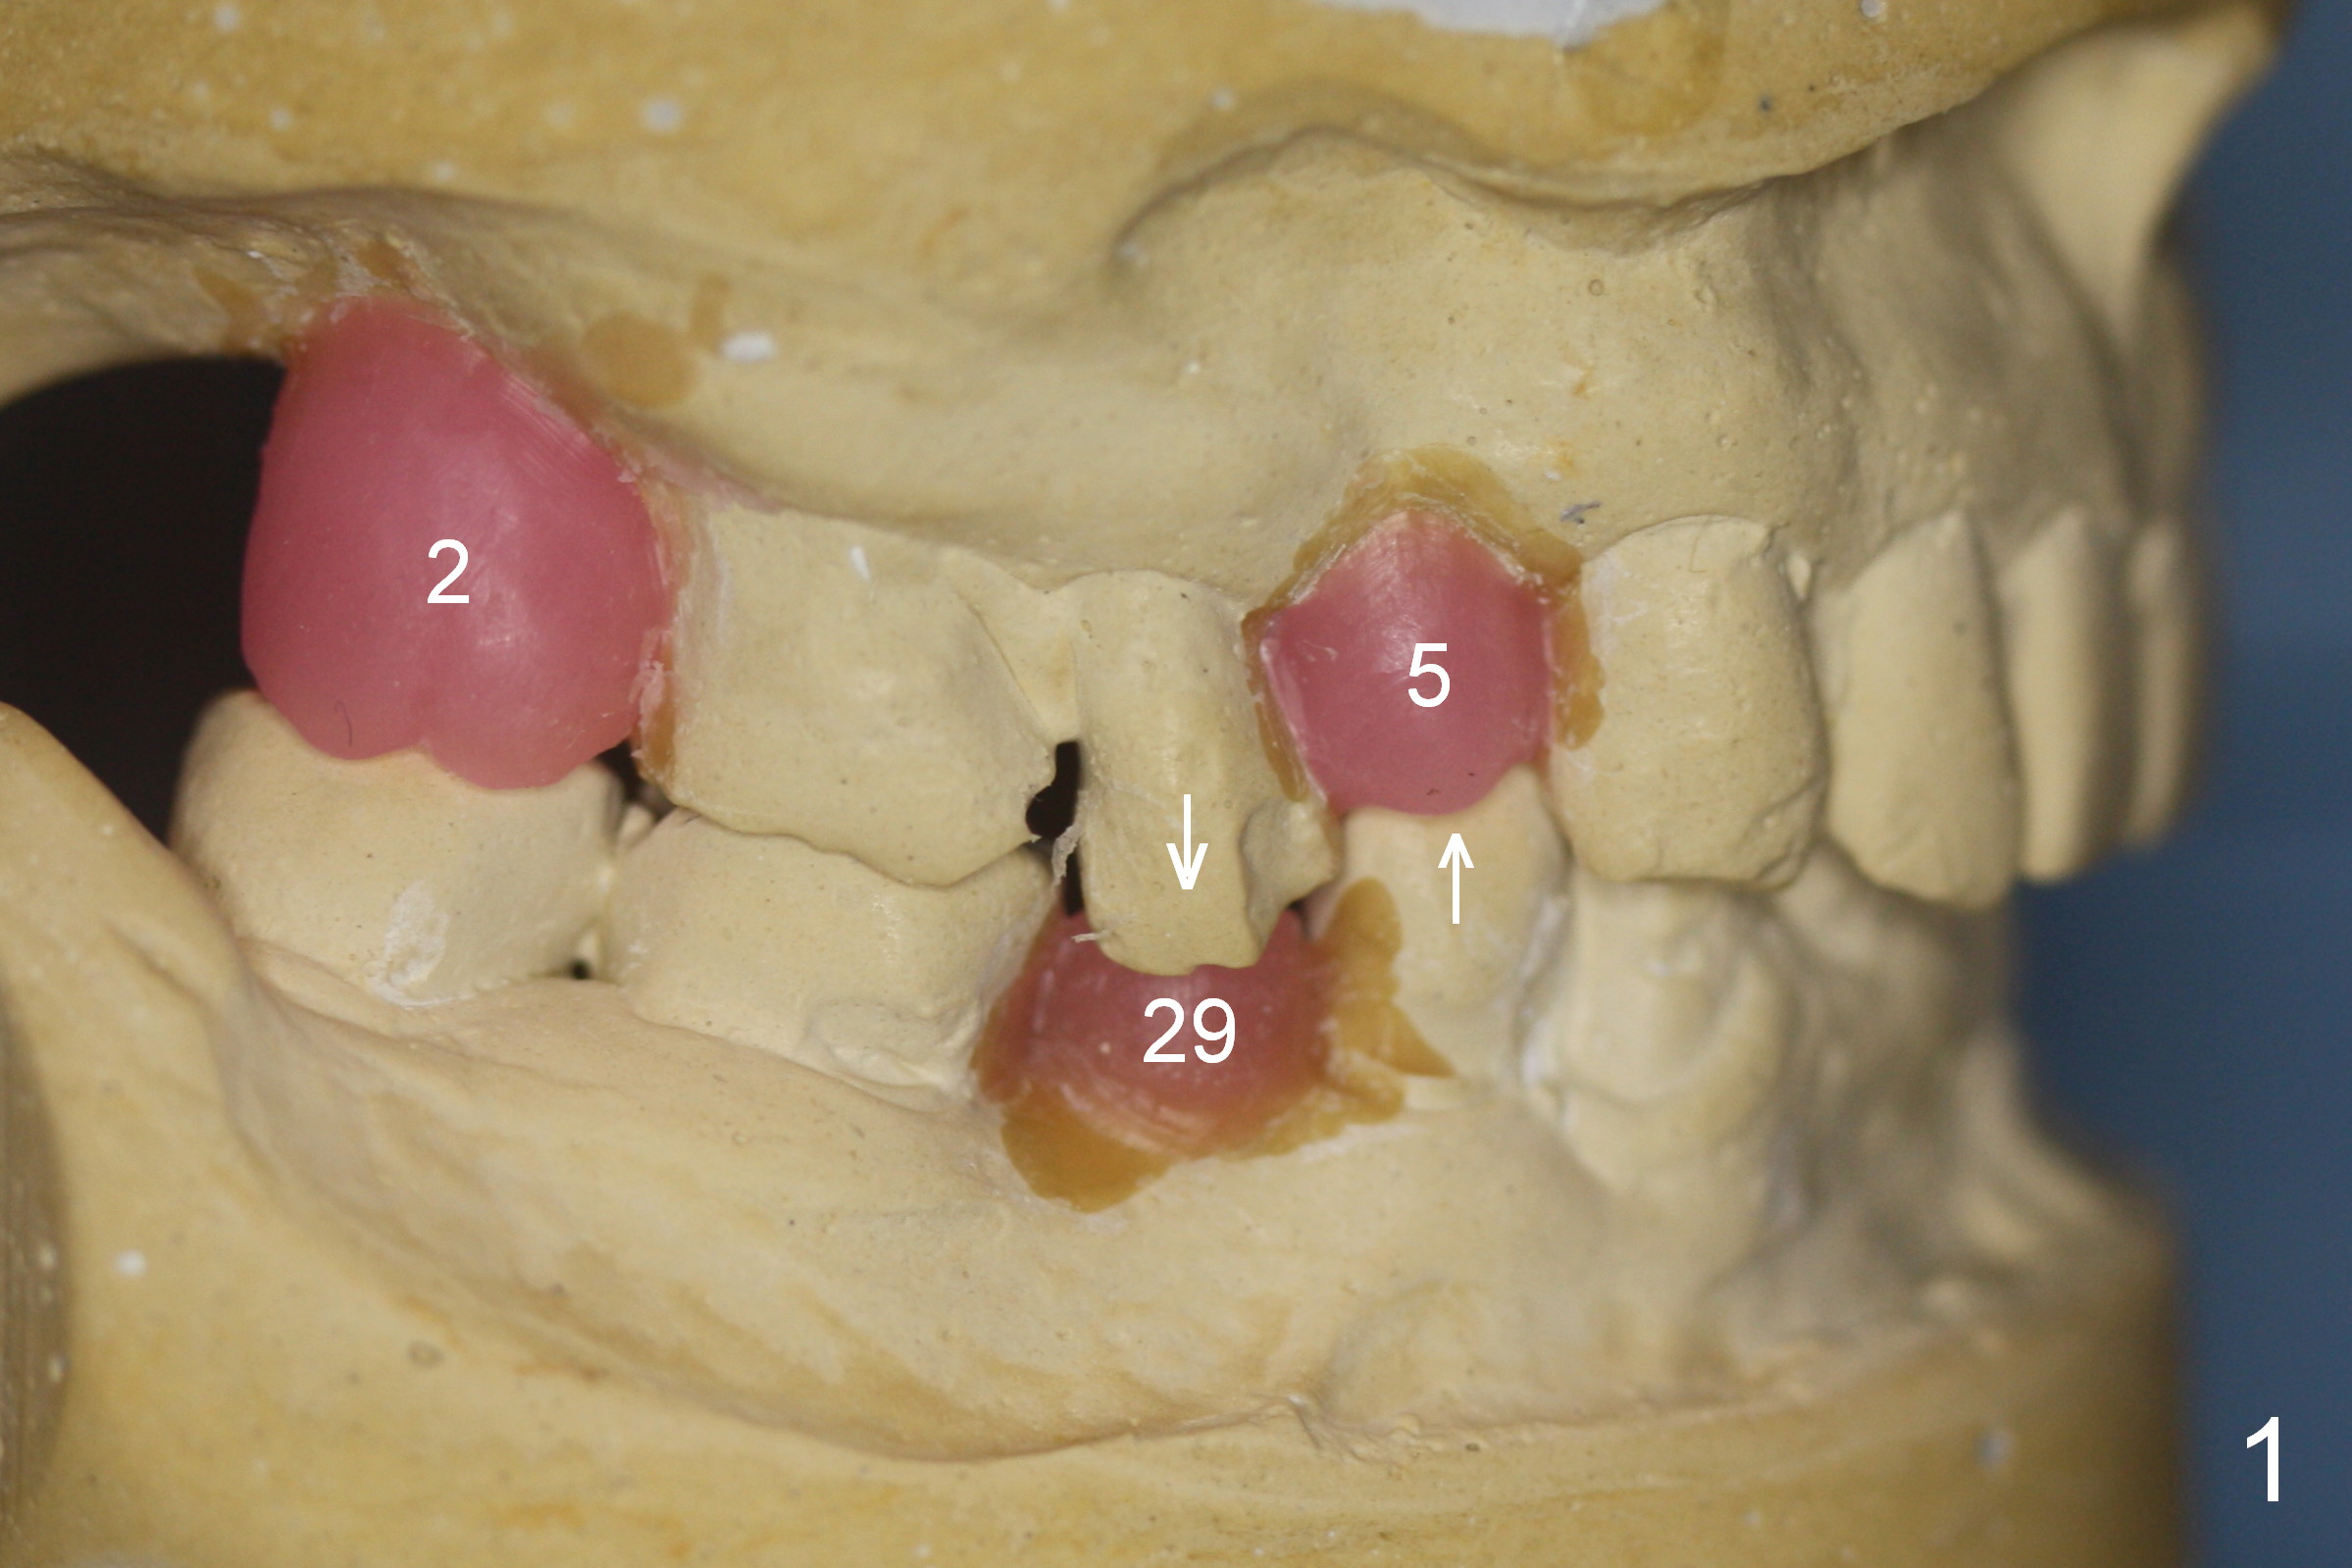

A 56-year-old man has long-termed partial edentulism (#2,5,14,15 (not shown),29, Fig.1). There is supraeruption of the opposing teeth (Fig.1 arrows). If an immediate provisional is provided, it should have plenty of clearance to avoid micromovement of the implant. Once the implants at #2,5, and 29 osteointegrate, they will be used as anchorage for intrusion (Fig.2,3 arrows, segmental orthodontics).